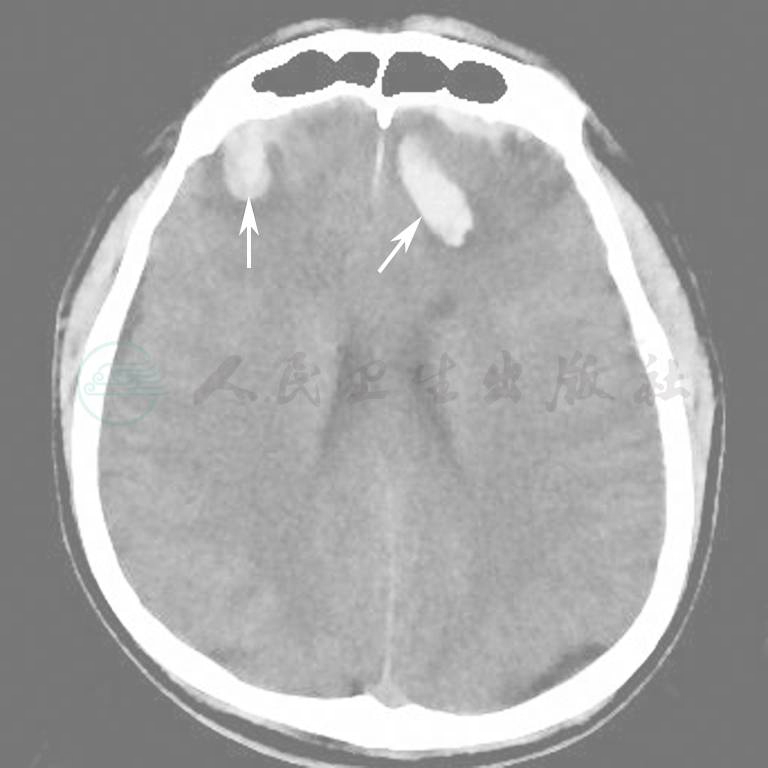

图15为颅脑外伤出血伴骨折病例。

图15  外伤后颅内出血(箭)

A.脑组织窗;B.骨窗;C.VR重建